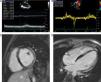

A 16-year-old male patient with known Becker's muscular dystrophy (BMD), with deletion of exon 48–49, was noted to have recent deterioration in already limited functional capacity. The transthoracic echocardiogram revealed moderately impaired left ventricular systolic function, with ejection fraction of 44% (Figure 1A), and preserved relaxation (Figure 1B). A cardiovascular magnetic resonance (CMR) study was performed and confirmed high-normal indexed left ventricular volumes with moderately reduced global ejection fraction (48%). No active inflammation was seen. Late gadolinium-enhanced images showed typical subepicardial fibrosis of the lateral and inferior wall from base to mid-ventricular level (Figure 1C and D).

(A) Transthoracic echocardiogram in parasternal view depicting a dilated left ventricle with moderately reduced ejection fraction. (B) Tissue Doppler imaging of lateral mitral inflow velocities, with an E/e′ ratio of 5.3, suggestive of normal filling pressures. (C and D) Cardiovascular magnetic resonance images with late gadolinium enhancement showing typical subepicardial inferolateral fibrosis (white arrows), also involving the mid-septum (dashed arrow), consistent with Becker's cardiomyopathy.